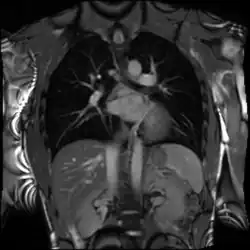

Cardiac magnetic resonance imaging (cardiac MRI, CMR), also known as cardiovascular MRI, is a magnetic resonance imaging (MRI) technology used for non-invasive assessment of the function and structure of the cardiovascular system.[2] Conditions in which it is performed include congenital heart disease, cardiomyopathies and valvular heart disease, diseases of the aorta such as dissection, aneurysm and coarctation, coronary heart disease. It can also be used to look at pulmonary veins.[3]

Combined with vasodilator stress, it has a role in detecting and characterizing myocardial ischemia due to disease affecting the epicardial vessels and microvasculature. Late gadolinium enhancement (LGE) and T1 mapping allow infarction and fibrosis to be identified for characterizing cardiomyopathy and assessing viability.[8] Magnetic resonance angiography may be performed with or without contrast medium and is used to assess congenital or acquired abnormalities of the coronary arteries and great vessels.[9]

4D flow CMR

Conventional phase contrast imaging can be extended by applying flow-sensitive gradients in 3 orthogonal planes within a 3D volume throughout the cardiac cycle. Such 4D imaging encodes the velocity of flowing blood at each voxel in the volume enabling fluid dynamics to be visualised using specialist software. Applications are in complex congenital heart disease and for research into cardiovascular flow characteristics - however it is not in routine clinical use due to the complexity of post-processing and relatively long acquisition times.[26]